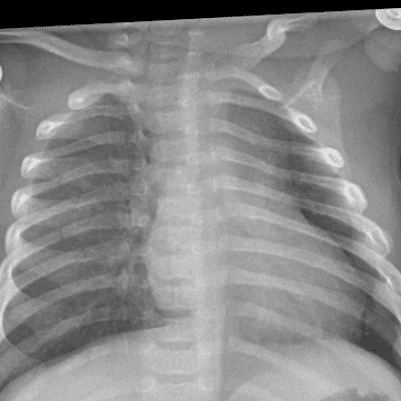

Peds Chest

Practice

Simulates call by including subtle or difficult cases and some normals.

50 cases